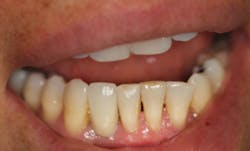

This is the case of a patient who has been missing a lower incisor for more than a year due to a failed root canal treatment (RCT). While there’s plenty of space mesiodistally, bone sounding helped us determine that there was only 4 mm of bone in the buccolingual dimension. A mini-implant was placed without raising a flap, the impression was taken at the time of surgery, and the implant was restored three weeks later.